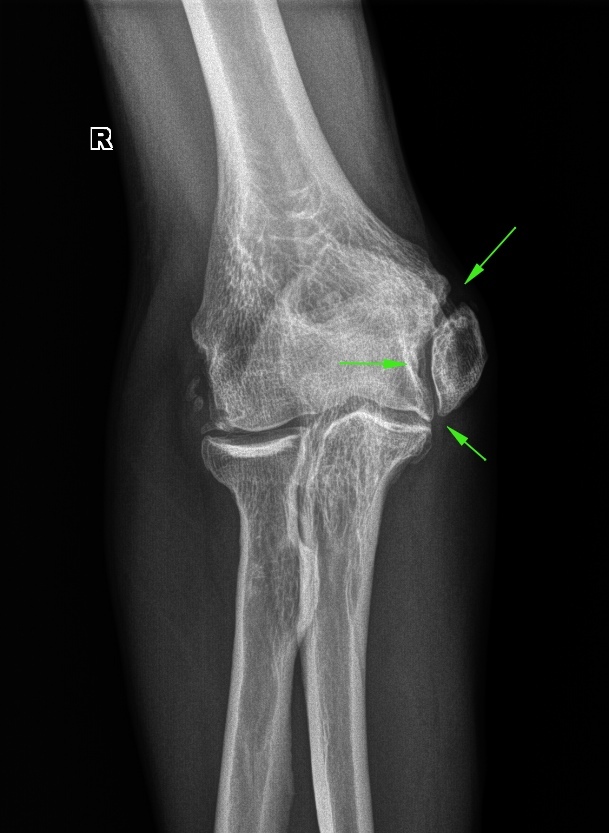

Оссификаты Локтевого Сустава: Диагностика и Лечение

Раздел: Секреты мастерства